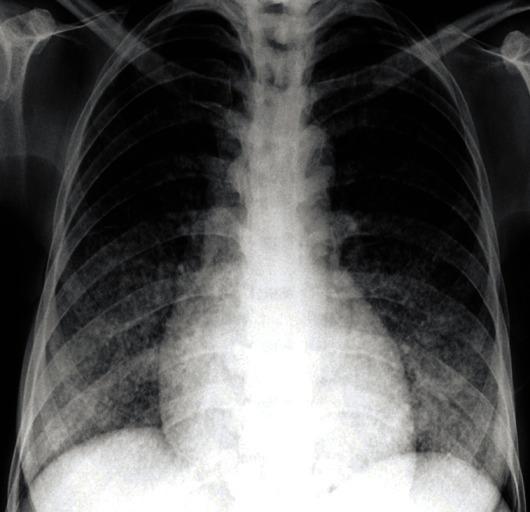

Endocrinopathy complicating a case of Tuberous sclerosis.

Indian J Endocrinol Metab. 2013 Jan;17(1):182-4. doi: 10.4103/2230-8210.107883.

Endocrinopathy complicating a case of Tuberous sclerosis.结节性硬化症合并内分泌病1例